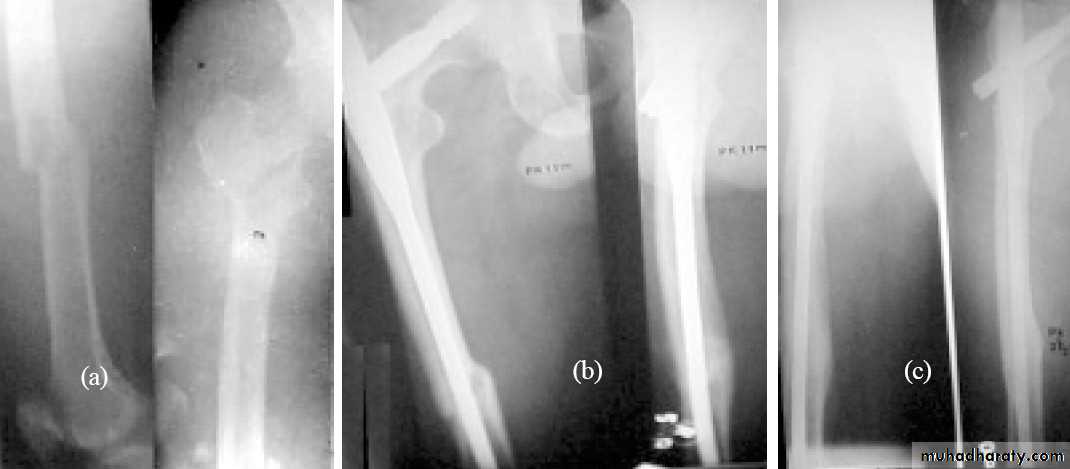

Inter-trochanteric fractures (extracapsular fracture)

.It is extra capsular fracture occurs in elderly.

.Unite quite easily and seldom cause a vascular necrosis.

Radiological examination

2 types

Stable.

Unstable.

Treatment:

Same previous principle almost always treated by early internal fixation.

(to overcome) the possible complications associated with prolonged recumbency.

To get the patient up and walking as soon as possible.

1.Sliding nail

2.L-plate

3.External fixation

Gamma nail

Postoperative exercise is started as early as possible on the

( day after operation ).

Patient is allowed up and partial weight bearing as soon as possible.